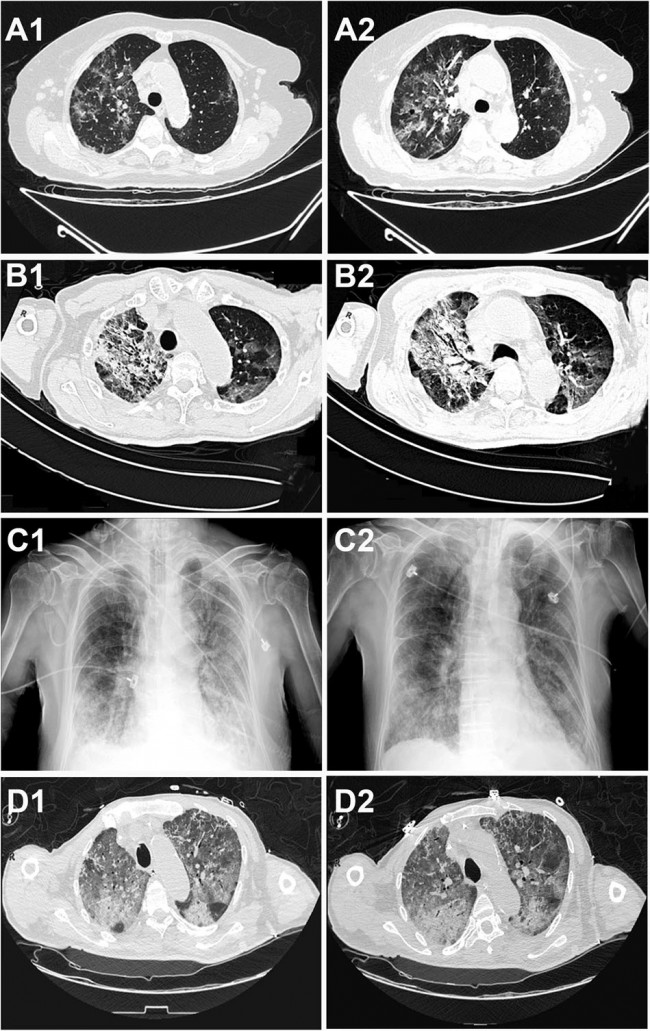

The solid flat-line demarcates the lower normal limit of lymphocyte count (1.1 × 109/L). In Case 1 (a) the elevated lymphocyte count is consistent with her history of chronic lymphocytic leukemia (CLL). Marked lymphocytopenia is seen in Cases 2, 3, and 4 (b, c, d). Fig. 2: Radiographic images of chest CT scan and X-ray from the four patients. For each patient, the left and right images represent an earlier and latter time-point, respectively.

Chest CT from Case 1 showed multiple patchy GGO in the bilateral upper lobes of the lungs and appeared more prominent in the right upper lobe (RUL) (A1). Repeat CT showed similar changes as A1 but with thickened fascicles of vasculatures and bronchi (A2). In Case 2, patchy GGO, consolidation, and air bronchogram can be seen in RUL; scattered GGO can be identified in the left upper lobe (LUL) (B1). Repeat CT showed additional consolidation in LUL (B2). In Case 3, X-ray showed patchy high-density shadows in both lungs, which were more prominent in the lower lobes (C1) and worsened during the couple of days before death (C2). In Case 4, diffuse GGO is seen in both lungs as well as consolidation in the posterior segment (D1), and additional air bronchogram can be detected in the later radiography (D2). Fig. 3: Histologic changes in the lungs.